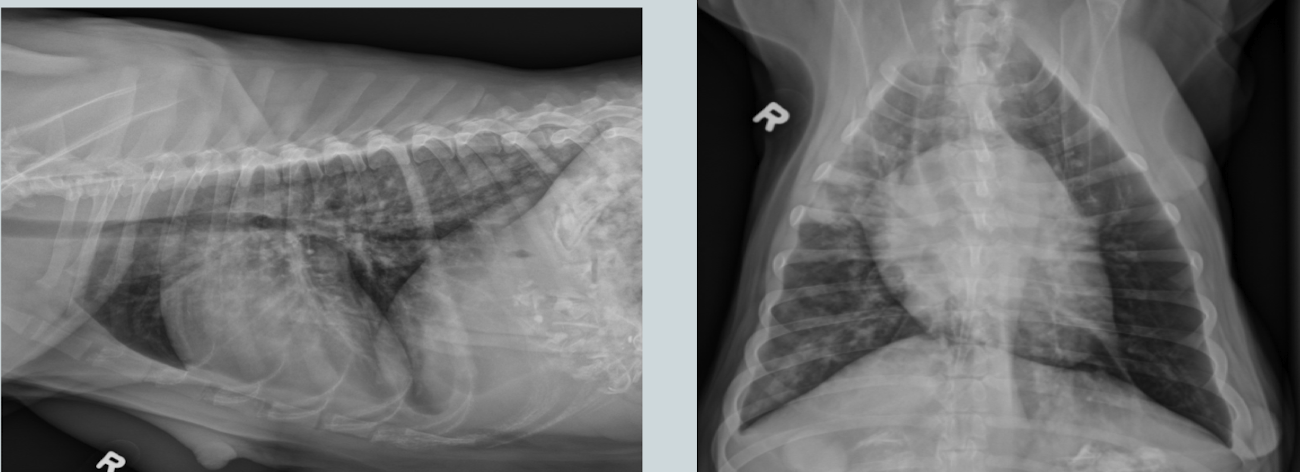

What condition? What main feature does the image show?

Stifle DJD (likely from a cruciate ligament rupture)

intracapsular swelling (cranial displacement of infra patellar fat pad and caudal displacement of fascial stripe)

What condition is this showing in a dog? How would it differ in a cat?

Cardiogenic edema (perihilar distribution)

Cat: would look patchy and mulitfocal anywhere (see image)